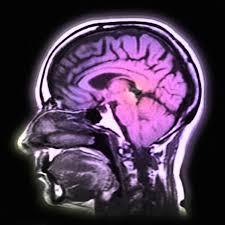

Jangkitan Kuman Di Otak : Abses otak atau abses serebri adalah penumpukan nanah akibat infeksi otak.

Kuman yang menjangkiti menyebabkan keradangan di kawasan yang terjejas. Jangkitan dan penyakit dalam badan boleh menyebabkan berlakunya uveitis. Ada yang memberi manfaat, seperti bakteria dalam usus yang membantu penghadaman. Hal ini kerana untuk menghilangkan semua kuman dan bakteria yang mungkin melekat pada badan kita. Walau bagaimanapun, sepsis juga boleh berpunca daripada jangkitan lain seperti virus. Kondisi ini bisa menyebabkan pembengkakan pada otak. Jangkitan ini biasanya cetek dan dilokalkan ke tisu lembut dan kulit di sekitar kuku. Jangkitan jari & jari bengkak: Otak dan saraf tunjang kita serta struktur di sekitarnya boleh dijangkiti oleh kuman yang luas spektrum. Paronichia adalah jangkitan jari yang melibatkan tisu di pinggir kuku. Selalunya pesakit akan merasa sakit di bahagian tersebut dan ia kerap berlaku pada kanak kanak. Abses otak sering ditandai dengan munculnya sakit kepala yang berat, demam, kejang, bahkan gangguan kesadaran. #jangkitan kuman dalam tekak punca anak demam terlalu tinggi sampai pucat bibir anak sebab demam tinggi sangat.cepat2 bawa emergnce.

Kuman yang menjangkiti menyebabkan keradangan di kawasan yang terjejas. Abses otak atau abses serebri adalah penumpukan nanah akibat infeksi otak. Saya serah pada pihak hospital dan kita lihat keadaan wani memang tidak berapa sihat semenjak pertemuan pertama. Kondisi ini bisa menyebabkan pembengkakan pada otak. Jangkitan dan penyakit dalam badan boleh menyebabkan berlakunya uveitis. Jangkitan kuman di otak (meningitis). Walau bagaimanapun, sepsis juga boleh berpunca daripada jangkitan lain seperti virus. Walau bagaimanapun, beberapa penyelidik perubatan dan ahli kesihatan mengesyaki bahawa kuman yang hidup di dalam otak mungkin menjadi punca alzheimer.